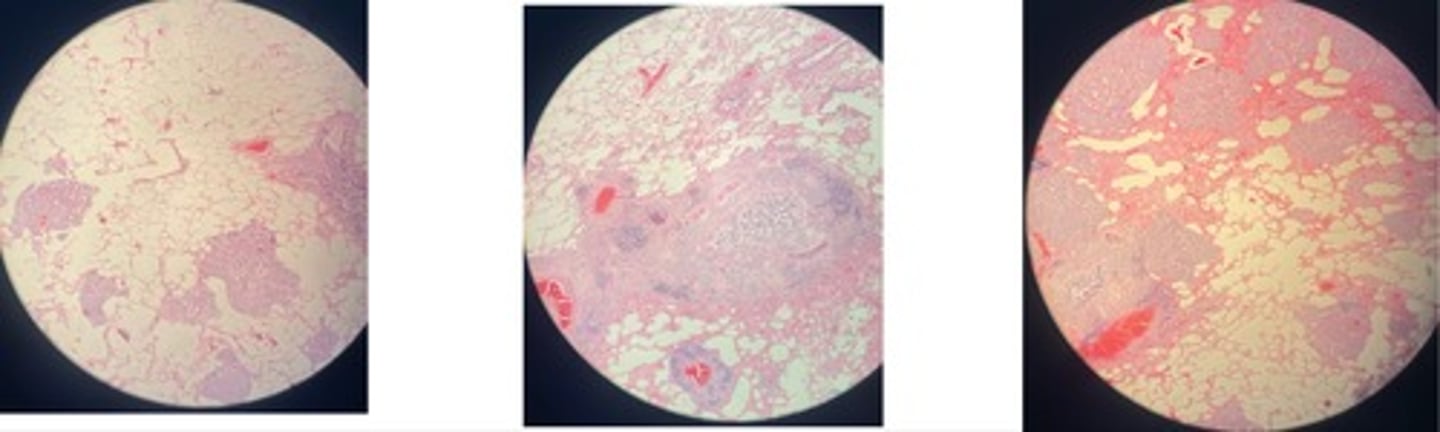

Catarrhal Bronchopneumonia

· thick bronchide walls

· catarral exudate in alveoli lumen (RBCs, leukocytes + mucous)

· congested vessels

· edema separates good + bad

Fibrinous Bronchopneumonia => mosaic appearance

· Acute = capillaries congested + alveoli filled w/light pink fluid

· Red = alveoli filled w/ exudate = fibrin + RBCs

· Grey = lots of neutrophils in lumen

· Resolution = fibrin in strands due to neutrophils enz release

Pulmonary tuberculosis

- central necrosis surrounded by epitheloid cells w/ giant cells btw

- infiltrates of lymphocytes, plasma, fibrosis